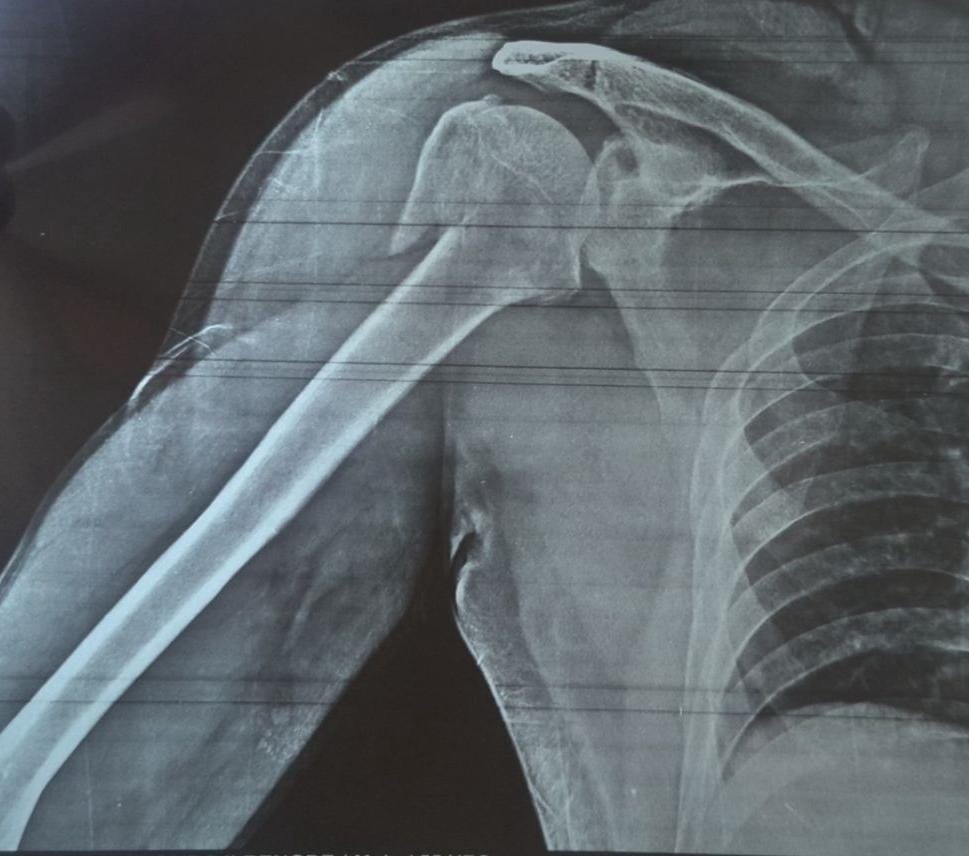

4 part Proximal humerus fracture treated with PHILOS plating !